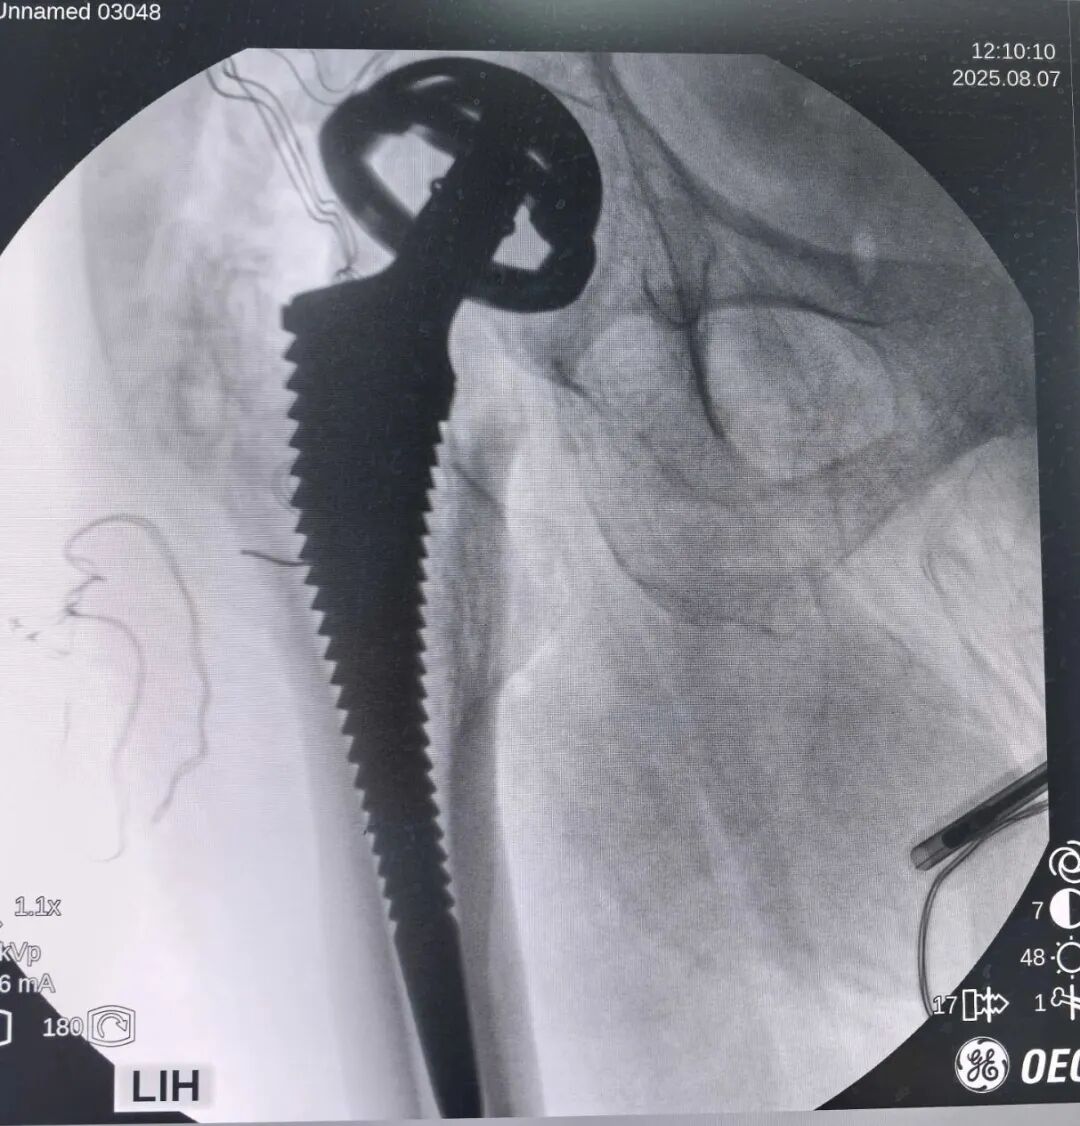

术前准备的各型扳手排上了用场,取出毫无困难。取出螺丝后纱布填塞。

用窄的骨刀在垫片周围挖坑,将垫片往骨头里锤击——暴露更多的钉尾——只要它能露头,取出就不是问题,免去了对不锈钢材料进行任何切割之苦。

空心环钻套住钉尾——卡住就行,歪着也无妨,借助电钻快速拧出!

主打一个不走寻常路,以退为进、歪打正着,完整、无损、快速取钉法。

这玩意,不知道是哪个厂家的,好歹取出来了,手术已经成功一半。